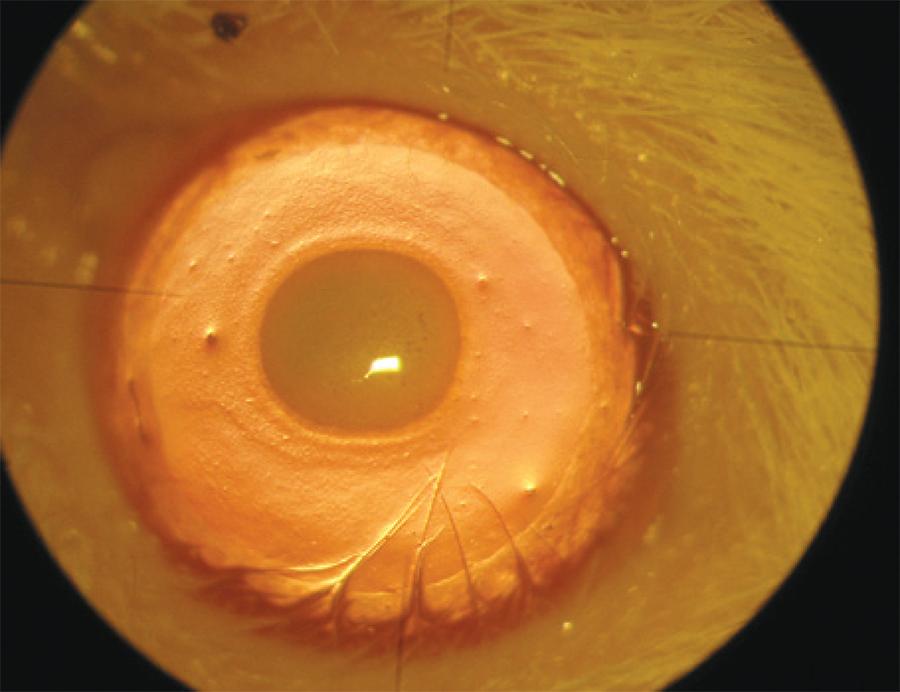

On the eighth day, a slit-lamp microscopy examination was performed and digital photographs were taken under anesthesia and analgesia (Figure 3). For each eye, the neovascularization response was evaluated toward the centrally placed burn from the entire corneal circumference, as follows: Grade 0, no visible vessels in cornea; Grade 1.5, 1/4 distance to burn; Grade 2, 1/3 distance to burn; Grade 3, 1/2 distance to burn; Grade 4, 2/3 distance to burn; Grade 4.5, 3/4 distance to burn; and Grade 6, vessels reach burn(14). The area of corneal neovascularization was analyzed using a software program (Matlab(tm) R2007b version 7.5, Math Works, Natick, Massachusetts, USA). An investigator who was blinded to the study groups initially drew blood vessel borders and cornea circumferences on the photographs. The program then calculated the total cornea area and the neovascularized area. It then estimated the percentage of corneal neovascularization (neovascularized area/total cornea area × 100).

Figure 3 Image of an eye with corneal neovascularization after eight days of treatment. A scar formation can be observed on the central cornea. Neovascularization begins at the limbus and continues towards the burn area.